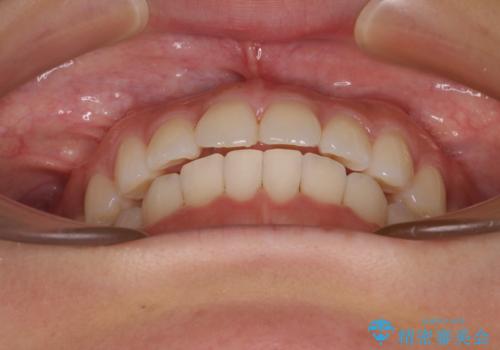

上下前歯のデコボコ ワイヤー装置で楽して改善

治療中は大きなトラブルもなく、予定の1年半でスムーズに治療を終えることができました。